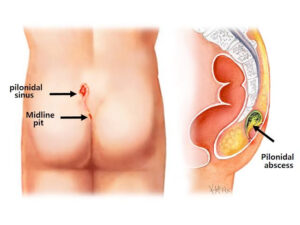

Read MorePilonidal sinus surgery

Pilonidal surgery refers to procedures used to treat pilonidal cysts,...

Read MoreAbcess Surgery

An abscess is a localized collection of pus within tissues,...